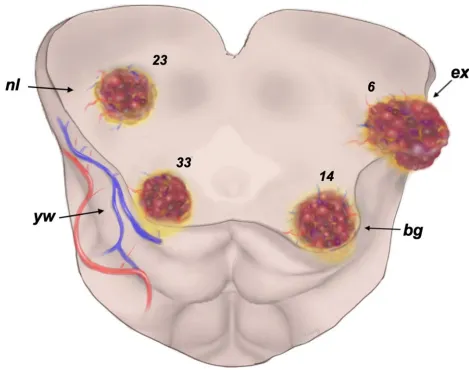

研究团队创新性地依据病灶与脑干表面的解剖位置关系,将中脑海绵状血管瘤系统性分为4种临床类型,实现病灶"隐匿程度"的精准分级评估:

nl型(深藏型):病灶完全位于中脑深部结构,脑干表面未出现任何异常病理改变,占比30.3%;

yw型(微染型):脑干表面仅见含铁血黄素沉积所致的微黄色染色改变,占比43.4%;

bg型(隆起型):病灶压迫脑干表面结构,形成轻微隆起性改变,占比18.4%;

ex型(外生型):病灶突破脑干表面结构,可直接进行观察,占比7.9%。

在传统医学认知体系中,nl型(深藏型)手术实施难度最高、临床风险最大,预后结果理应最差。

但研究数据呈现反转性结果:nl型患者术前mRS神经功能评分(评分分值越低,代表神经功能状态越好)平均为1.43分,术后长期随访评分降至0.61分,已接近健康人群水平;其神经功能恢复效果,甚至优于部分位置更为表浅的bg型、ex型患者群体。